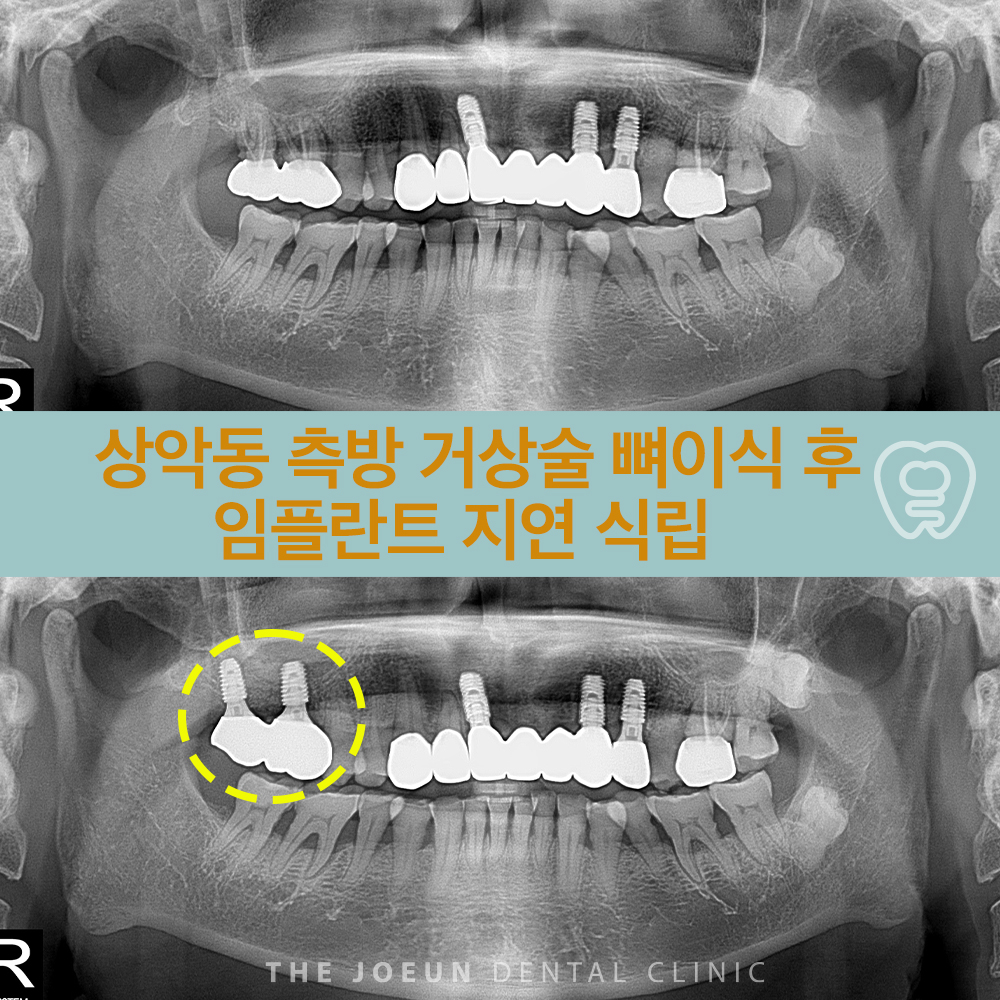

강창역치과 상악동 측방 거상술 뼈이식 후 임플란트 지연 식립

강창역치과 상악동 측방 거상술 뼈이식 후 임플란트 지연 식립 윗니 어금니 부위에 존재하는 상악동에 대해…